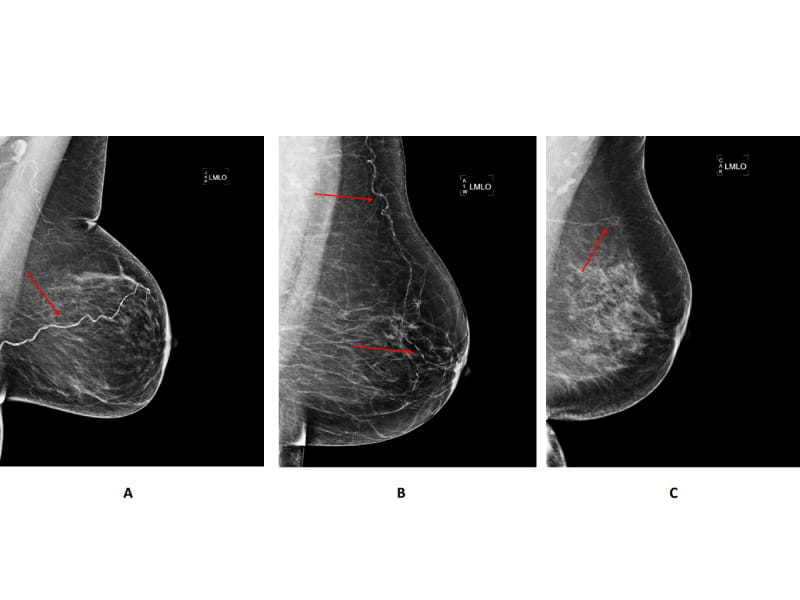

Researchers found that breast arterial calcification, which commonly appears as white spots on breast images and indicates a buildup of calcium in the arteries, is associated with an increased risk for developing cardiovascular disease. The findings published Tuesday in the American Heart Association journal Circulation: Cardiovascular Imaging.

Breast arterial calcification can occur as women age and is related to Type 2 diabetes, high blood pressure and inflammation. It is a marker for stiffening arteries but is not the same type of calcification found in the inner layer of the arteries that is caused by smoking or high cholesterol levels. The appearance of calcification during breast imaging may be overlooked because it isn't believed to signal the presence of breast cancer.